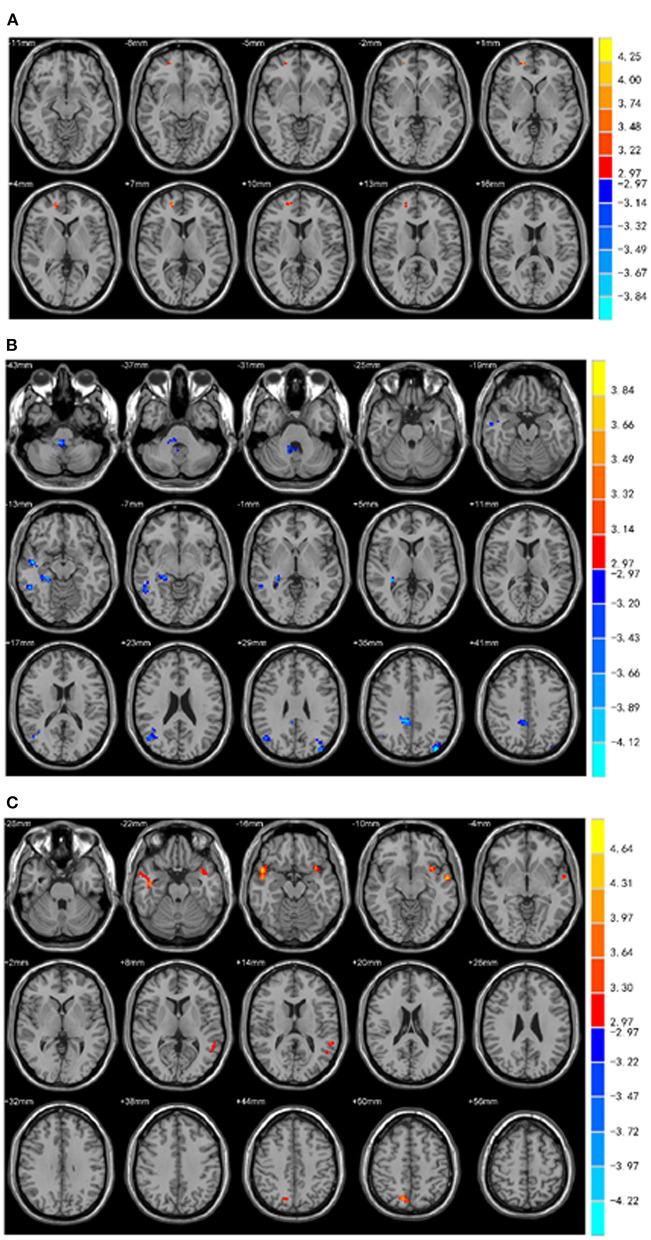

PD-EDS patients exhibited a decreased fALFF in the Cingulum-Ant-R, but an increased fALFF in the Putamen-R and Thalamus-L when compared with PD-NEDS patients; an increased functional connectivity between these three seed regions with different fALFF values and the right medial frontal gyrus, bilateral superior temporal gyrus, left insular, and right precuneus was observed ( < 0.05), but a deceased functional connectivity between these three seed regions and the right cerebellum anterior lobe/right brainstem, right middle temporal gyrus and inferior temporal gyrus, right hippocampus/parahippocampal gyrus, right medial cingulate gyrus and bilateral middle occipital gyrus was observed ( < 0.05). The value of fALFF was negatively correlated with the ESS score in the Cingulum-Ant-R, but positively correlated with the ESS score in the Putamen-R and Thalamus-L.

与PD-NEDS患者相比,PD-EDS患者扣带回前束右侧(Cingulum-Ant-R)的fALFF降低,但壳核右侧(Putamen-R)和丘脑左侧(Thalamus-L)的fALFF升高;观察到这三个具有不同fALFF值的种子区域与右侧内侧前额叶回、双侧颞上回、左侧岛叶和右侧楔前叶之间的功能连接增加(P < 0.05),但观察到这三个种子区域与右侧小脑前叶/右侧脑干、右侧颞中回和颞下回、右侧海马/海马旁回、右侧内侧扣带回和双侧枕中回之间的功能连接减少(P < 0.05)。Cingulum-Ant-R的fALFF值与ESS评分呈负相关,但Putamen-R和Thalamus-L的fALFF值与ESS评分呈正相关。